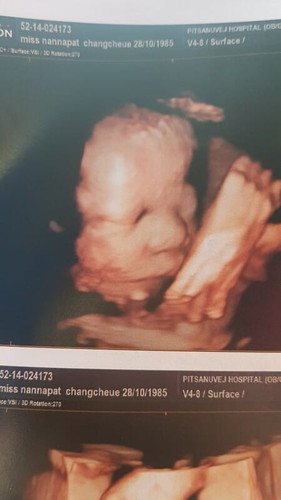

กำลังตั้งครรภ์ (แม่พี่กิ๊บ)